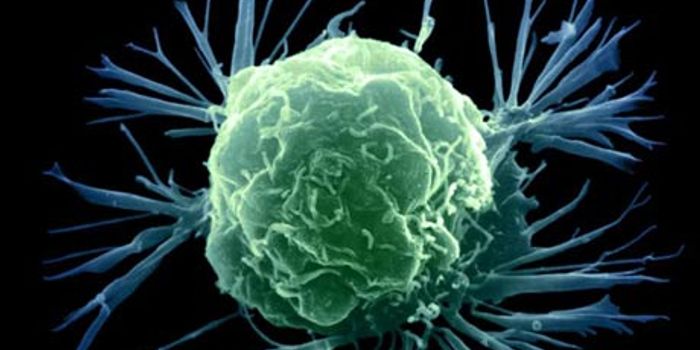

JUN 29, 2017CancerMost cancers kill by invading distant parts of the body where treatment is more difficult to reach. But cancer’s a ...

OCT 19, 2017CancerTo fuel their growth and edge out healthy cells, breast cancer cells recycle a waste product into nutrients, researchers ...